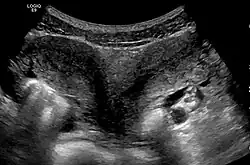

- The two Müllerian ducts have fused, but the partition between them is still present, splitting the system into two parts. With a complete septum the vagina, cervix and the uterus can be partitioned. Usually the septum affects only the cranial part of the uterus. A uterine septum is the most common uterine malformation and a cause for miscarriages. It is diagnosed by medical image techniques, i.e. ultrasound or an MRI. MRI is considered the preferred modality due to its multiplanar capabilities as well as its ability to evaluate the uterine contour, junctional zone, and other pelvic anatomy. A hysterosalpingogram is not considered as useful due to the inability of the technique to evaluate the exterior contour of the uterus and distinguish between a bicornuate and septate uterus. This condition can be complete or partial

Besides a physical examination, the physician will need imaging techniques to determine the character of the malformation: gynecologic ultrasonography, pelvic MRI, or hysterosalpingography. A hysterosalpingogram is not considered as useful due to the inability of the technique to evaluate the exterior contour of the uterus and distinguish between a bicornuate and septate uterus. In addition, laparoscopy and/or hysteroscopy may be indicated. In some patients the vaginal development may be affected.